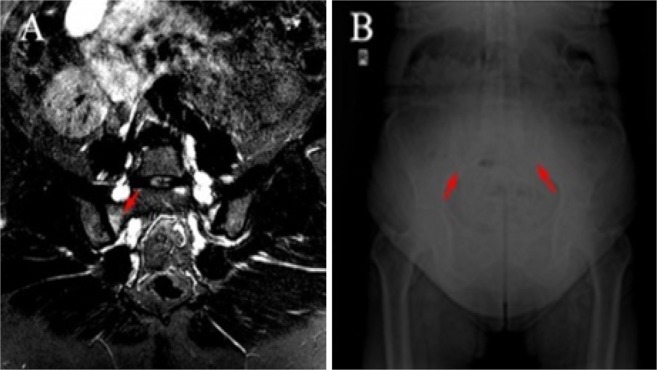

Figure 1.

(A) STIR (short tau inversion recovery) sequence of MRI showing bone marrow edema in the sacroiliac joint of an acromegaly patient. (B) X-ray film showing sclerosis and partial ankylosis in the sacroiliac joint of an acromegaly patient.

From the MRI of sacroiliac joints, 12 (36.4%) patients had no abnormalities (Table 2). Fatty marrow deposition and sclerosis occurred 33.3 and 18.2% of the acromegaly patients, respectively. None had erosions. Active sacroiliitis was detected in 4 (12.1%) of those examined for sacroiliac MRI (Fig. 1). One was enthesitis and 3 (9.1%) were BME. BME lesions in 2 (6.1%) patients met the ASAS MRI working group’s criteria for defining sacroiliitis by MRI13. Thus, 3.1% of our acromegaly patients met radiographic axial SPA classification criteria, and 6.1% met non-radiographic axSpA classification criteria14.